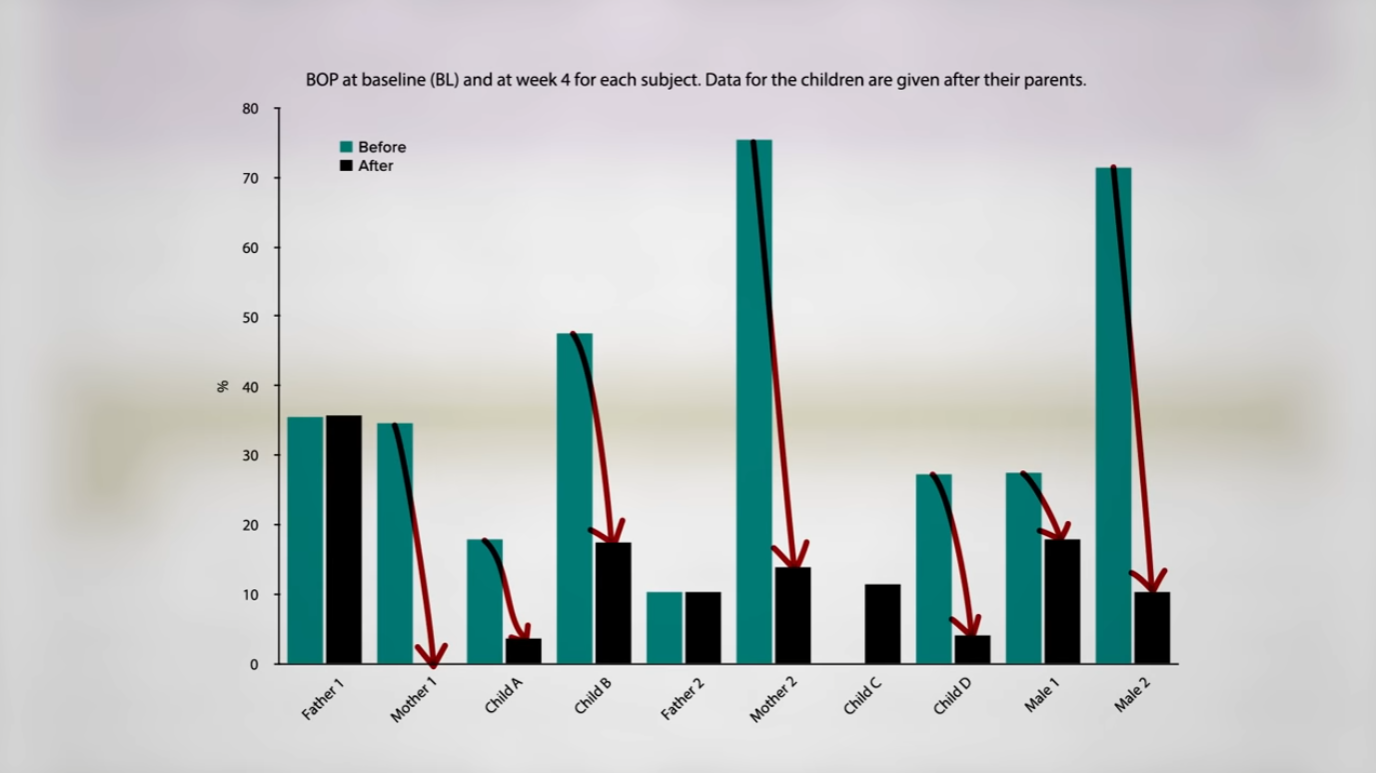

With no oral hygiene, their plaque built up, as you can see in the graph below and at 1:53 in my video, but their gums got healthier, as measured by bleeding on probing. (Gums bleeding when poked with a dental tool is a measure of gingivitis.) In almost every case, the participants’ gum health improved. How is it possible that their gums were actually healthier despite buildup of plaque? Many of the more disease-causing bacteria seemed to have disappeared from their mouths. The researchers suggested this could be from the lack of refined sugars, but the participants were eating honey, so they weren’t on a sugar-free diet. They were, however, eating a lot of whole grains and berries rich in antioxidant phytonutrients with anti-inflammatory properties. So, maybe it was restricted sugar intake combined with the intake of really healthy foods. Thus, all of those experimental studies where people stop brushing their teeth and their gums inevitably get inflamed “may only be applicable if the subjects maintain a Western diet rich in sugar and low in anti-inflammatory foods,” such as whole plant foods.